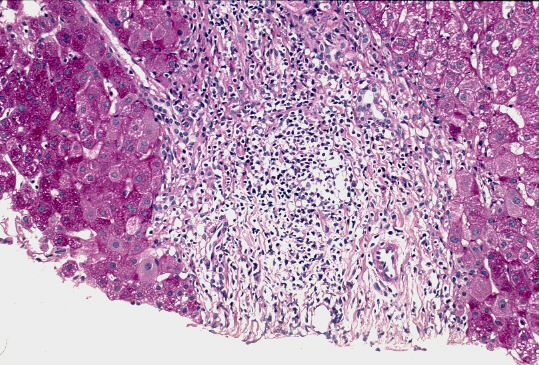

標 本;HE、Masson-trichrome、PAS&鍍銀の4染色

- 小葉構造;保持されている[F1〜(2)]、一部のP-Pのapproximation

- 門脈域;中等度の線維性拡大、中等度の単核球主体の炎症性細胞浸潤、リンパ様濾胞、明らかな小葉間胆管の障害像、periductal fibrosis、細胆管増生

- 実質域;acute yellow collapse cell を含む巣状壊死を散在性にみる、好酸体(+)、肝細胞の風船様膨化と明調化(部分的)、肝細胞の大小不同、肝細胞核の大小不同、大滴性脂肪沈着を部分的に軽度にみる、核内空胞、ロゼット形成(偽腺管構造)、実質内に細線維の伸長、一部の限界板の削り取り壊死、銅の沈着はなし。

病理組織診断;Acute exacerbation of chronic hepatitis [AIH]

A(2)〜3/F1〜(2) [AIH]

病 因;元来、軽度の慢性炎に急性増悪が加わったAIH